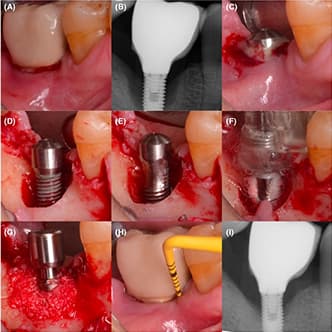

Accelerated Osseointegration: Effect of the Pulsed Electromagnetic Field (PEMF) on Dental Implants Stability, A Randomized Controlled Clinical Trial

A randomized controlled clinical trial assessed the effect of PEMF on the stability of 40 dental implants in 20 patients. The test group showed a significant 13% increase in implant stability, compared to a 2% decrease in the control group.